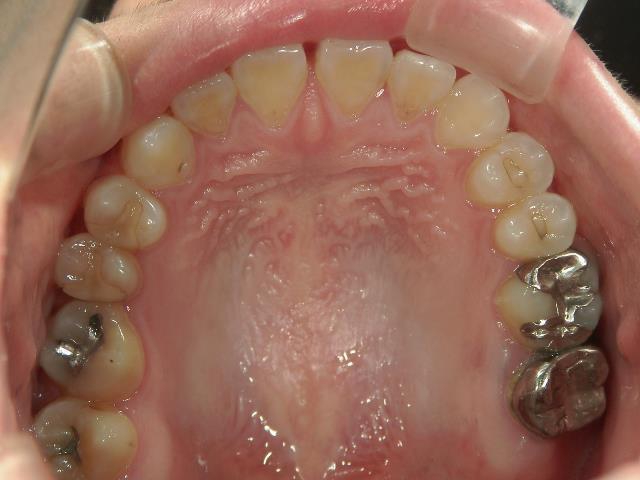

矯正歯科 治療前 急速拡大装置で上顎を広げた後、ワイヤーへ移行 非抜歯

矯正歯科 治療後

矯正_灰色.pngno.31_7964_治療後_上.JPG矯正_灰色.png